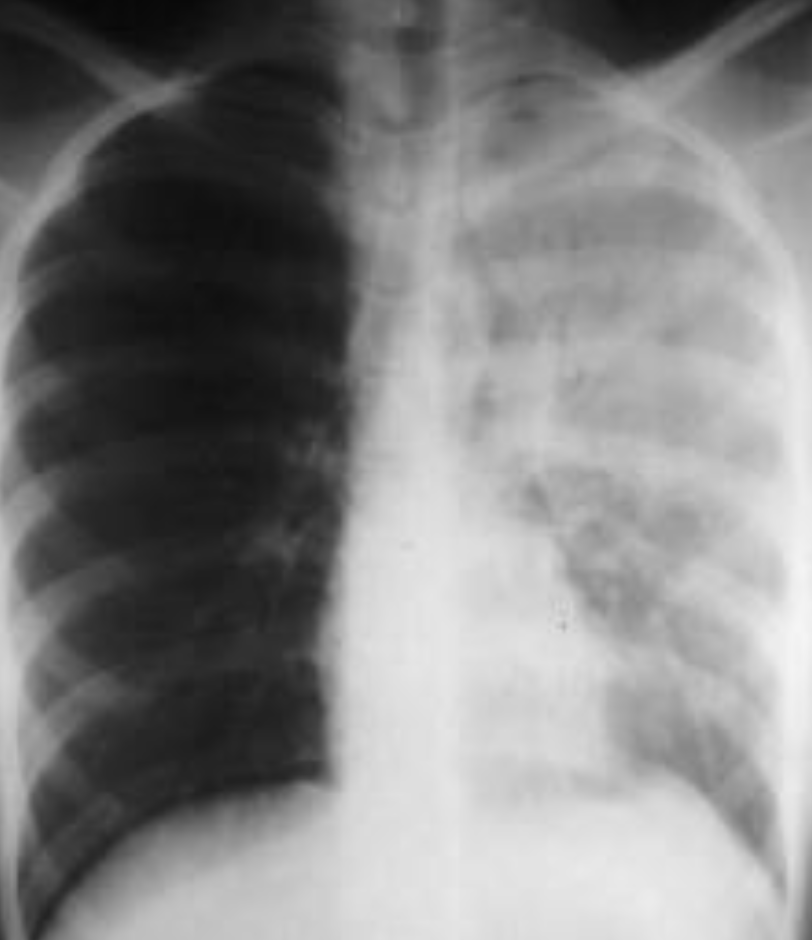

RESPIRATORY AND CARDIOVASCULAR RADIOPLOGY

A. What is the most likely diagnosis in the given images; RT lower lobe pneumonia

B. Which lobe of the lung affected by this disease in the given image. Lower lobe, reverse change of opacity from spine

A. What is the most likely diagnosis in the given images

pneumonia ex… due fever cough and the imaging

B. Which lobe of the lung affected by this disease in the given image. Right middle Lobe Lesion, due obliteration of diaphragm - and lateral of horizontal fissure opaque

Pneumonia most common due to no deviations of midline - could be truama, ectopy, etc… so follow through with case given for diagnosis

- The left hemithorax is opaque

- There is no shift of the heart or trachea

- The opacified hemithorax contains air bronchogram

- No loss of lung volume